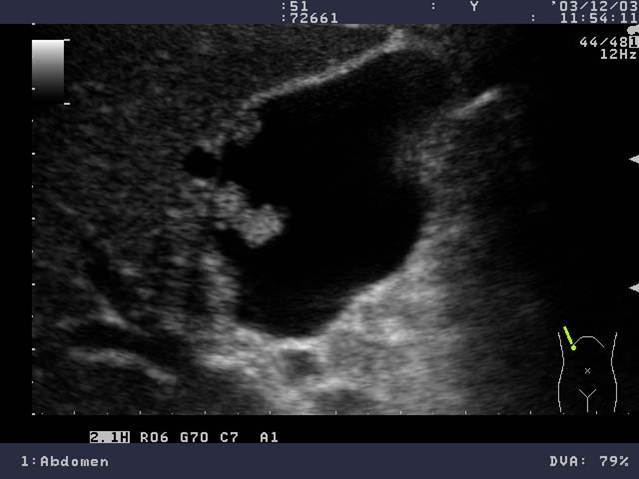

Cholelithiasis

(These small stones are “floating” on sludge

This is layering)